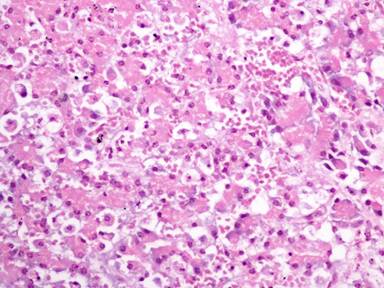

The results of the histopathological evaluation are presented in Table 1. No statistically significant differences were noted concerning edema (P=0.563), hemorrhage (P=0.241), leukocyte infiltration (P=0.256), acinar necrosis (P=0.231) and vacuolization (P=0.438) between the two groups. Figures 1 and 2 present representative pathological cases.

Figure 2. Effects of acute ischemia and reperfusion on pancreatic histology. The main feature in this field is the distortion of pancreatic histology. Note the significant hemorrhage, the moderate interlobular and intralobular edema and the presence of some necrotic foci (15-35%). H&E x400. |